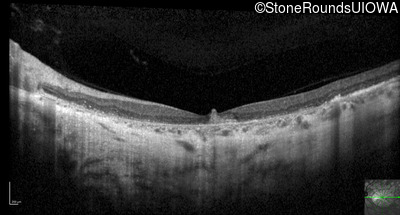

Optical Coherence Tomography - Right - 20/63

Exemplar / OCT Stack